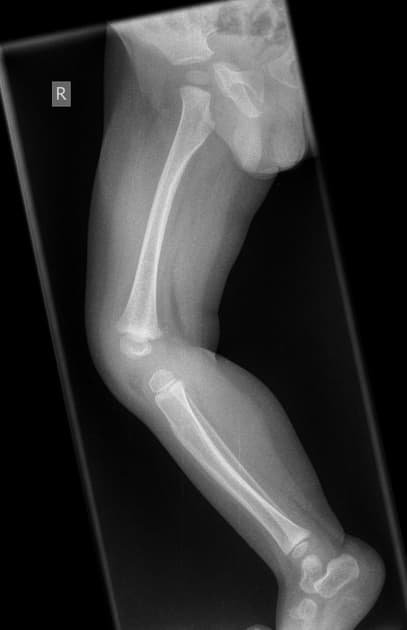

Lower Limb Pediatric

Lower Limb (Pediatric) Projections Patient Preparation Explain the procedure gently to both the child and guardian.. Remove any clothing, shoes, or metallic objects from the area of interest.. Immobilization aids or parental assistance may be used for comfort and to prevent motion.. Use appropriate ...

Read more →